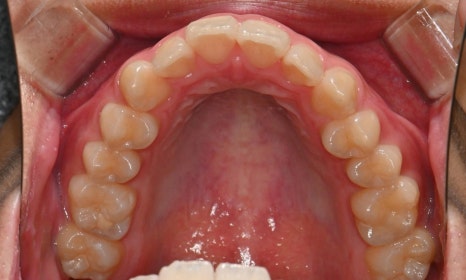

2024.12. 초진 구내사진 - 연세정원치과

정밀 검진 결과, 하악 치열이 좌측으로 틀어져 있었고 그로 인해 위아래 치아 중심선이 일치하지 않았습니다. 아래 치열이 전체적으로 전방 위치하여 아래 입술 돌출이 더 도드라져 보이는 상태였습니다. 그리고 상악궁이 하악궁보다 좁아서 앞니 부위 일부 반대로 물리는 치아 교합도 관찰되었습니다. 특히 외상 치아의 경우, 교정력 적용시 추가적인 염증성 치근 흡수 위험이 존재하기 때문에, 치료 중 지속적인 관찰이 필수적인 상황이었습니다.